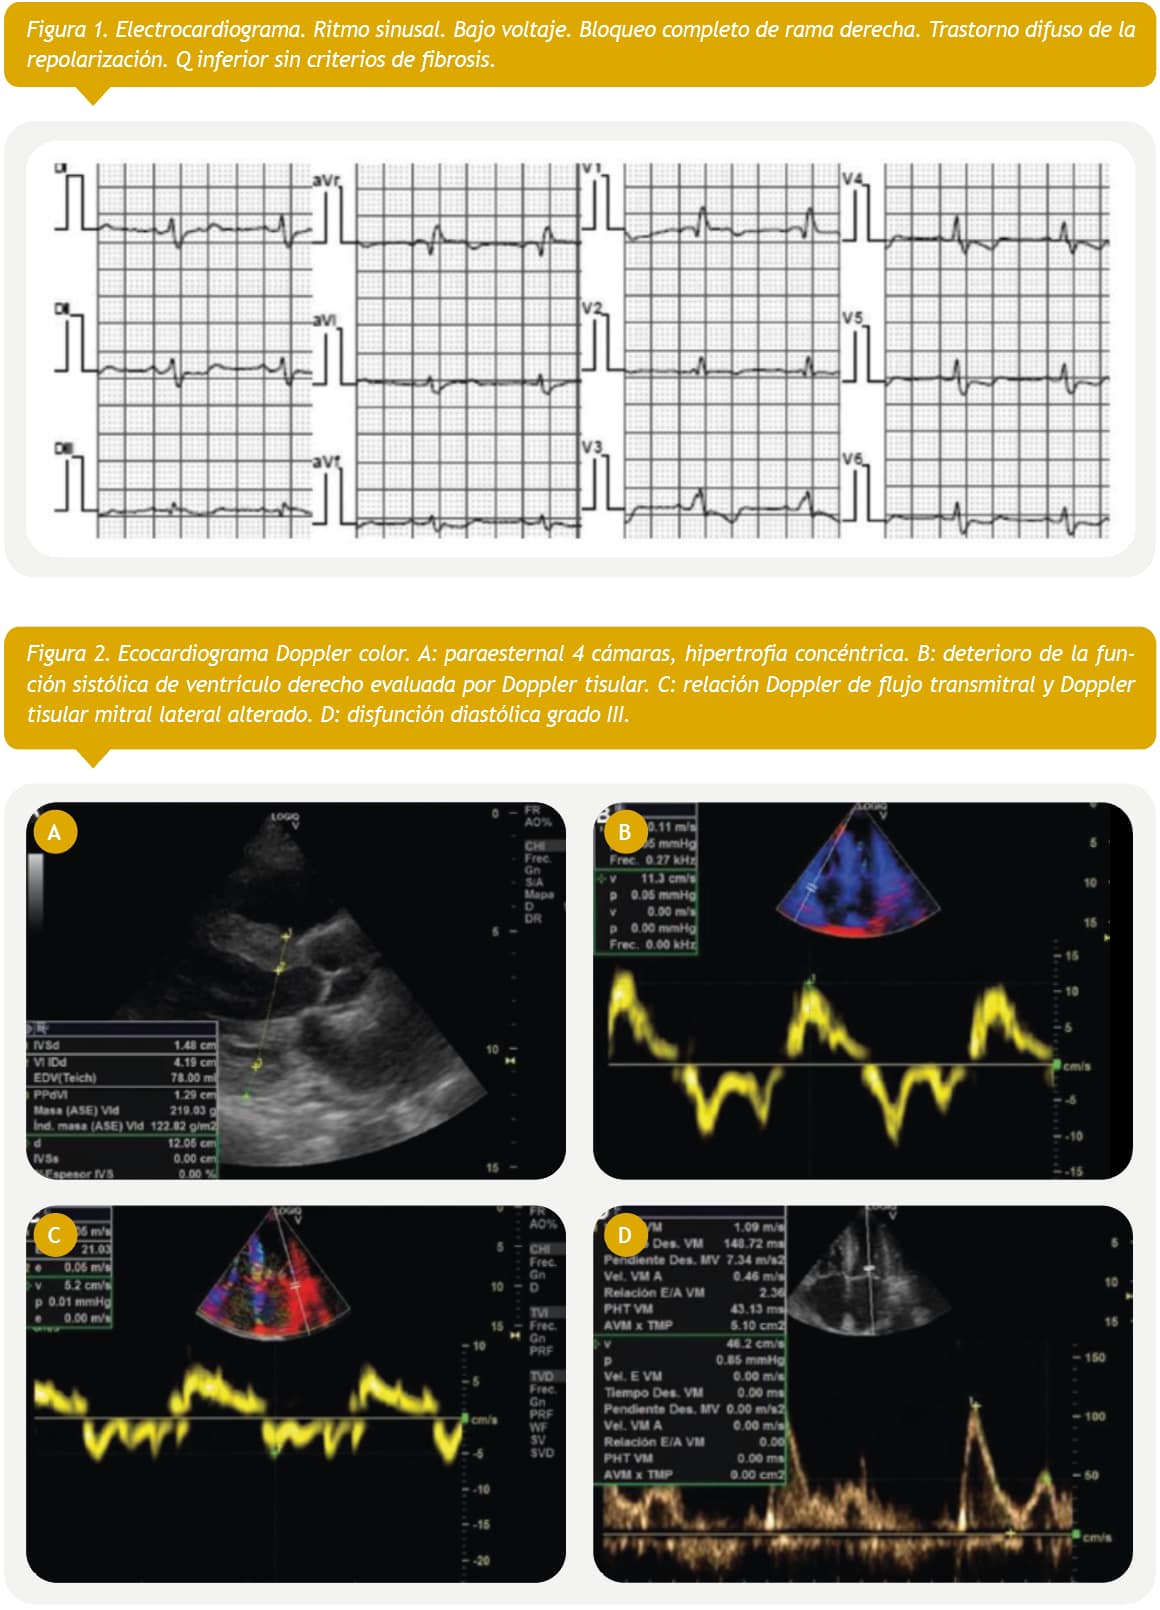

Paciente femenino de 67 años de edad, en seguimiento por hematología por anemia de cinco años de evolución, a quien se le realiza punción de médula ósea en la que se evidencian células plasmáticas con fenotipo alterado (> 10%) y concluye en el diagnóstico de mieloma múltiple. La analítica general y específica se resume en tabla 1. Evoluciona con clínica tórpida, desarrollando signos de IC por lo que se solicita electrocardiograma (Fig. 1), ecocardiograma Doppler color (Fig. 2) y resonancia magnética nuclear cardiaca. Esta última informa: ventrículo izquierdo no dilatado, leve incremento de espesor parietal septal (12 mm), fracción de eyección de ventrículo izquierdo: 51%. IM leve, AI moderadamente dilatada. Fibrosis difusa transmural inferoseptal basal e inferoseptal medial, fibrosis subendocárdica en pared inferior de ventrículo derecho. Valores de T1 mapping nativo aumentados en forma difusa (valores mayores a 1110 ms). Volumen extracelular (VEC) 55%, hallazgos compatibles con AC. Por referir palpitaciones se solicita estudio holter de 24 horas (Fig. 3). Se diagnostica mieloma múltiple y AC con IC función sistólica preservada, iniciando tratamiento dirigido a ambas enfermedades. En su seguimiento presenta mejoría clínica de la función renal y cardiaca; luego de dos meses de tratamiento, las mediciones de NT-pro BNP y troponina I ultrasensible habían descendido un 30%. En ecocardiograma control se puede objetivar mejoría de la función diastólica, progresando desde una disfunción diastólica III (flujo transmitral tipo restrictivo) a una tipo I (flujo transmitral prolongado), mejoría en Doppler tisular y parámetros de deformación longitudinal global.

Electrocardiograma

La afectación del sistema de conducción es más común en la amiloidosis por transtiretina. Cambios característicos son el bajo voltaje frontal, especialmente si en otros exámenes como en el ecocardiograma, hay signos de hipertrofia y ondas Q en precordiales (aunque también pueden verse en derivaciones del plano axial) con un patrón conocido como pseudoinfarto o pseudofibrosis, el cual tiene implicaciones negativas en el pronóstico señalando menor sobrevida a un año y mayor impacto estructural9. Pueden observarse ectopias supraventriculares y ventriculares, siendo la arritmia más frecuente la fibrilación auricular y el flutter auricular (20%), habitualmente con trastornos de conducción (PR prolongado, bloqueo AV completo en 3%, trastornos de conducción intraventricular inespecíficos)10.

Ecocardiograma

Lo característico de esta enfermedad es que el infiltrado afecta aurículas y tabique interauricular, aumento simétrico del espesor parietal ventricular derecho e izquierdo con un aspecto brillante moteado tipo granular y sistema de conducción. Los cambios para comenzar a considerar el diagnóstico diferencial de AC son la relación Ee´ > 9.6, el volumen auricular izquierdo indexado y la disminución en la fracción de contractilidad miocárdica o fracción de acortamiento. Además, entre otros parámetros habituales pueden citarse el índice de excentricidad o espesor parietal relativo, ?ya que el fenotipo habitual en los pacientes con AC es de hipertrofia ventricular izquierda (HVI) concéntrica?, y el engrosamiento difuso valvar13.

Inicialmente, disminuye la complacencia auricular y aumenta la presión intraauricular, lo que lleva a que se ocupe menor tiempo tanto en el llenado ventricular como en el auricular. El descenso del llenado diastólico precoz es compensado por un enérgico llenado diastólico final, lo que, en estadios avanzados de la enfermedad, se traduce en una pseudonormalizacion del patrón. Por otro lado, otros autores han observado que la progresión de la enfermedad conlleva deterioro precoz de la diástole, pero no puede diferenciarse si este cambio se debe al envejecimiento normal celular. Es decir, que pueden observarse un patrón transmitral tipo pseudonormal, más habitual, o un patrón prolongado, el cual deberá diferenciarse de los cambios producidos por el envejecimiento. Otro aspecto a considerar es la afectación de la válvula mitral, ya que se ha observado una alta prevalencia de insuficiencia mitral que altera el patrón de llenado ventricular. Conforme avanza la enfermedad también se observan cambios en el patrón de las venas pulmonares. La evaluación de la función diastólica se correlaciona con la gravedad de la enfermedad y puede ser utilizada en su seguimiento14,15.